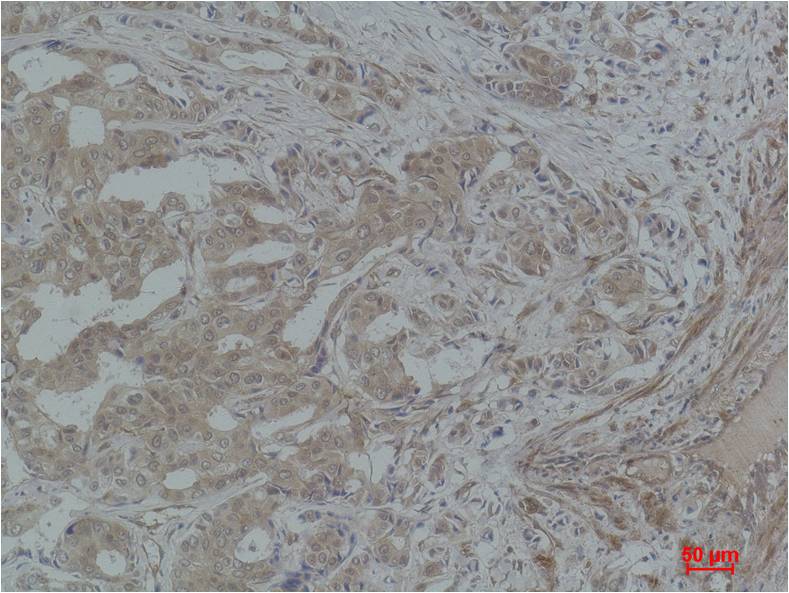

Product name: STAT3 Rabbit pAb

Dilutions: WB 1:1,000-2,000??? IHC? 1:200-500

Background: Signal transducer and activator of transcription 3, also known as STAT3, is a transcription factor which in humans is encoded by the STAT3 gene. Stat3 is constitutively activated in a number of human tumors and possesses oncogenic potential and anti-apoptotic activities.